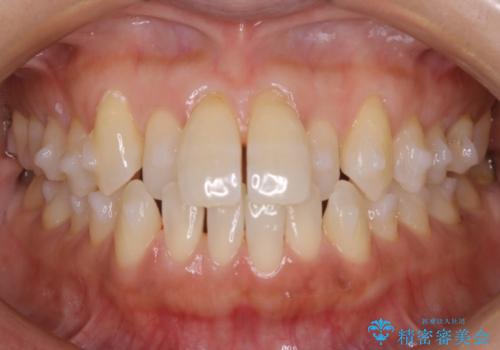

【非抜歯】短期間で実現する前歯の反対咬合治療

- 前歯のガタつきを主訴に来院されました。

奥歯の噛み合わせにはほとんど問題が見られず、歯列拡大とIPRのみの必要最低限の移動で歯並びの治療を計画することとなりました。